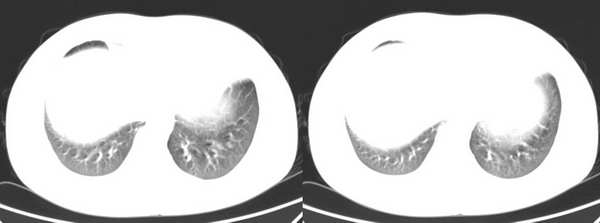

男,18岁。咳嗽,胸闷4天。

没有纵隔窗很难定的

肺转移